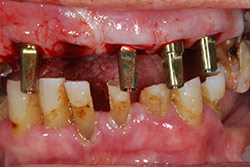

I denti irrecuperabili dell'arcata superiore ed inferiore del paziente di anni 65

sono stati sostituiti da 10 impianti, cioè protesi radicolari endo-ossee che sostengono le protesi fisse superiore ed inferiore.